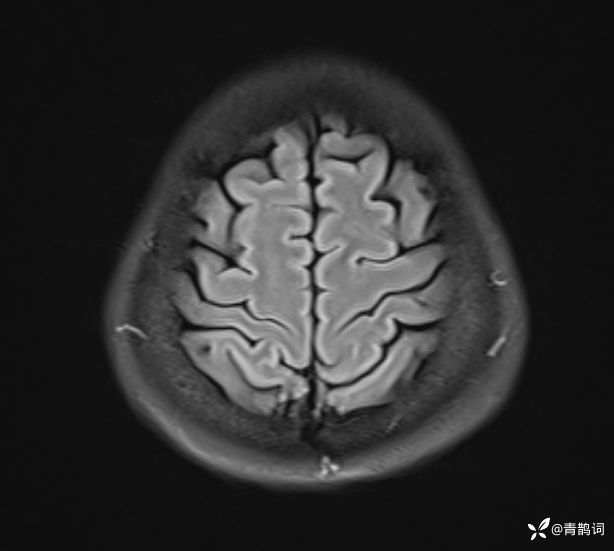

入院后完善磁共振:

FLAIR: